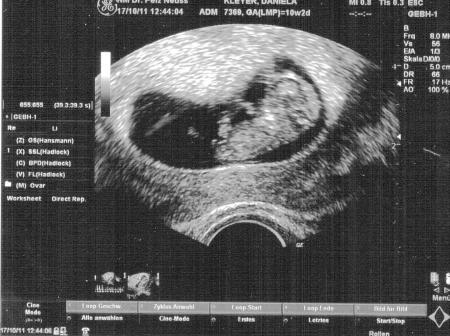

Hallo, endlich hatte ich mein Termin gehabt. Dem Krümel geht es sehr gut. Ist jetzt 3 cm groß und Zeitgerecht entwickelt. Habe heute endlich mein Mutterpass bekommen. Muss in drei Wochen wieder dort hin wegen meine Bluthochdruck. Krümel war auch sehr aktiv hat sich sehr viel bewegt. Lg Dani